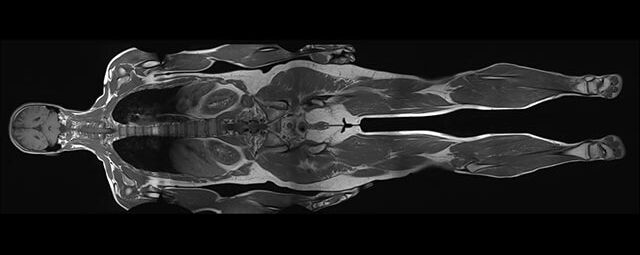

Im Magnetresonanztomographen liegt die zu untersuchende Person in einem starken, homogenen Magnetfeld. Dieses Magnetfeld bewirkt eine gemeinsame Ausrichtung der Wasserstoffprotonen im Körper entlang der Längsachse des Magnetfeldes. Wird nun diesen Teilchen Energie in Form von Radiowellen in einer genau abgegrenzten Frequenz zugeführt, so werden sie aus ihrer ursprünglichen Orientierung abgelenkt.

Die zugeführte Energie wird in gewebespezifischer Weise wieder abgegeben. Ein hochempfindliches Computersystem misst die unterschiedliche Energieabgabe und setzt sie in Bildinformationen um. Jede Körperregion kann somit durch Schnittbilder in allen Raumebenen oder durch dreidimensionale Rekonstruktionen mit einem exzellenten Weichteilkontrast dargestellt werden. Es besteht keine Belastung durch Röntgenstrahlen.

MR-Angiografie (MRA)

Angiographie ohne Kontrastmittel

• MR-Angiografie ohne Kontrastmittel

• Time of Flight (TOF)-Angiographie

• Phasenkontrastangiographie (PCA). Geeignet zur Quantifizierung Stenose-/Insuffizienzgrad z.B. bei Herzklappen, falls echokardiographisch die Untersuchungsbedingungen eingeschränkt sind.

Je nach Fragestellung und Körperregion Gefäßdarstellung ohne Kontrastmittel bei Kontrastmittelunverträglichkeit oder terminaler Niereninsuffizienz möglich.

Ganzkörper Angiographie mit Kontrastmittel

• MR-Angiographie mit Kontrastmittel

• Erfassung arterieller und venöser Gefäße/Bypässe aller Körperregionen mit 3D-Rekonstruktion

• je nach klinischer Fragestellung zeitaufgelöste MR-Angiographie (4D-MRA) z.B. bei Frage arteriovenöse Fistel/ Shunt oder Darstellung Unterschenkelarterien vor geplanter Bypassoperation.